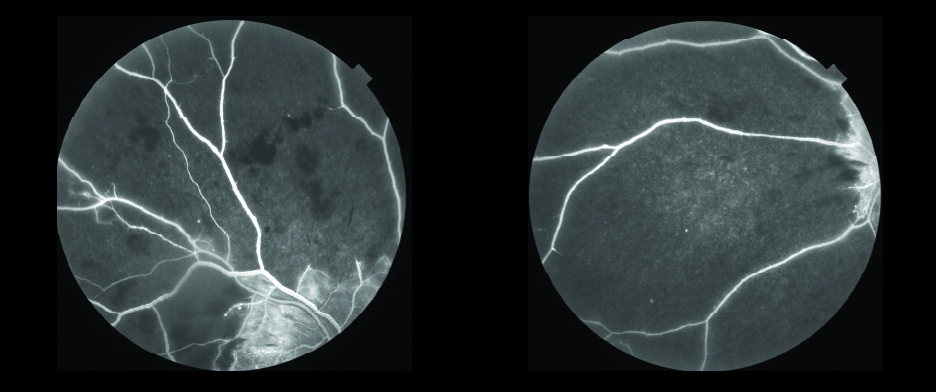

Case Study – Advanced PDR with Non-Perfusion and Macular Edema

3D Wide OCT Combination Scans, fluorescein angiography and fundus photos were obtained OU. Macular edema, subretinal fluid, intraretinal hemorrhages, cotton wool spots (CWS), nonperfusionable vessels and hemorrhages in the peripheral vessels were visualized OU.

Diagnosis: Advanced Proliferative Diabetic Retinopathy (PDR), retinal non-perfusion and macular edema OU

Discussion: 45-degree fluorescein images, true-color photos of the retina and penetrating swept-source OCT scans helped to confirm and document the clinical findings